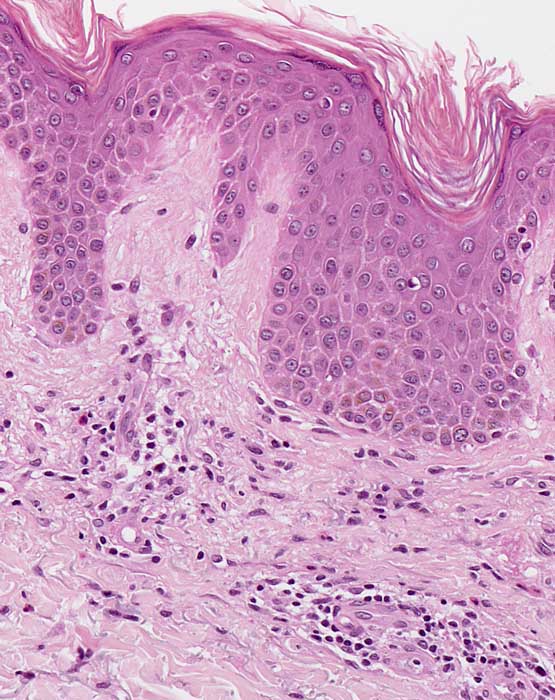

Mikroskopische Befunde:

Histologisch zeigen akute Ekzeme eine ausgeprägte Spongiose mit intraepithelialer Bläschenbildung, eine Parakeratose und Krustenauflagerungen, im chronischen Stadium eine Verminderung der Spongiose, eine Akanthose und Hyperparakeratose. Bei alten Läsionen können Parakeratosehügel und eine Epidermishyperplasie der einzige Hinweis auf eine spongiotische Dermatitis sein. Die Epidermishyperplasie ist teilweise eine Folge des chronischen Reibens und Kratzens der juckenden Haut. Das Entzündungsinfiltrat in der oberen Dermis besteht aus Lymphozyten und Histiozyten, zum Teil auch aus neutrophilen und eosinophilen Granulozyten. In der Epidermis dominieren Lymphozyten (lymphozytäre Exozytose). Akute, subakute und chronische Veränderungen können beim gleichen Patienten nebeneinander vorkommen.

Morphologische Merkmale:

• Verdickte Epidermis (Akanthose)

• Spongiose (interzelluläres Ödem der Epidermis)

• Spongiotische Vesikel (intraepitheliale Bläschenbildung)

• Parakeratotische Verhornung (Verhornte Zellen mit erkennbaren Zellkernen)

• Ödem der papillären Dermis (Aufhellung)

• Oberflächlich dermales perivaskulär betontes Entzündungsinfiltrat

• Lymphozyten, Histiozyten, neutrophile und eosinophile Granulozyten